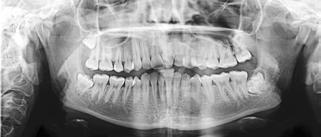

FORSKERE FRA ODONTOLOGISK INSTITUT (Københavns Universitet) har undersøgt, hvor meget ekstra information man kan få ved at supplere den kliniske registrering af primær caries, sekundær caries og restaureringssvigt med bitewingoptagelser (BW).

Kliniske og radiologiske data fra 240 personer (20 mænd og 20 kvinder i hver af seks aldersgrupper fra 19 til 83 år) indgik i undersøgelsen. Personerne var tilfældigt udvalgt blandt 4.402 deltagere i en stor dansk befolkningsundersøgelse (DANHES 2007-2008).

Blandt 907 ikkerestaurerede okklusalflader var der 110 med primær caries

I alt blev der analyseret 3.015 okklusalflader og 5.112 approksimalflader. Blandt 907 ikke-restaurerede okklusalflader var der 110 med primær caries, og 53 % af dem blev fundet på BW. 183 ud af 2.108 restaurerede okklusalflader havde sekundær caries, og 99 % af dem blev fundet på BW. 190 okklusale restaureringer var overeller underekstenderede, og 89 % af dem blev fundet på BW. Blandt 2.649 ikkerestaurerede approksimalflader var der 648 med primær caries, og 92 % af dem blev fundet på BW. 565 ud af 2.463 restaurerede approksimalflader havde sekundær caries, og 99 % af dem blev fundet på BW. 638 approksimale restaureringer var over- eller underekstenderede, og 98 % af dem blev fundet på BW.

Forfatterne konkluderer, at bitewingoptagelser er et afgørende supplement til klinisk cariesdiagnostik i alle aldersgrupper. Røntgenoptagelserne medvirker til, at man ikke overser primær caries hos unge patienter og sekundær caries hos midaldrende og ældre patienter.

Ved første undersøgelse af en ny patient bør man derfor supplere de kliniske registreringer med røntgenoptagelser for at få det fulde overblik over cariessituationen og fyldningskvaliteten okklusalt og approksimalt i de posteriore områder.